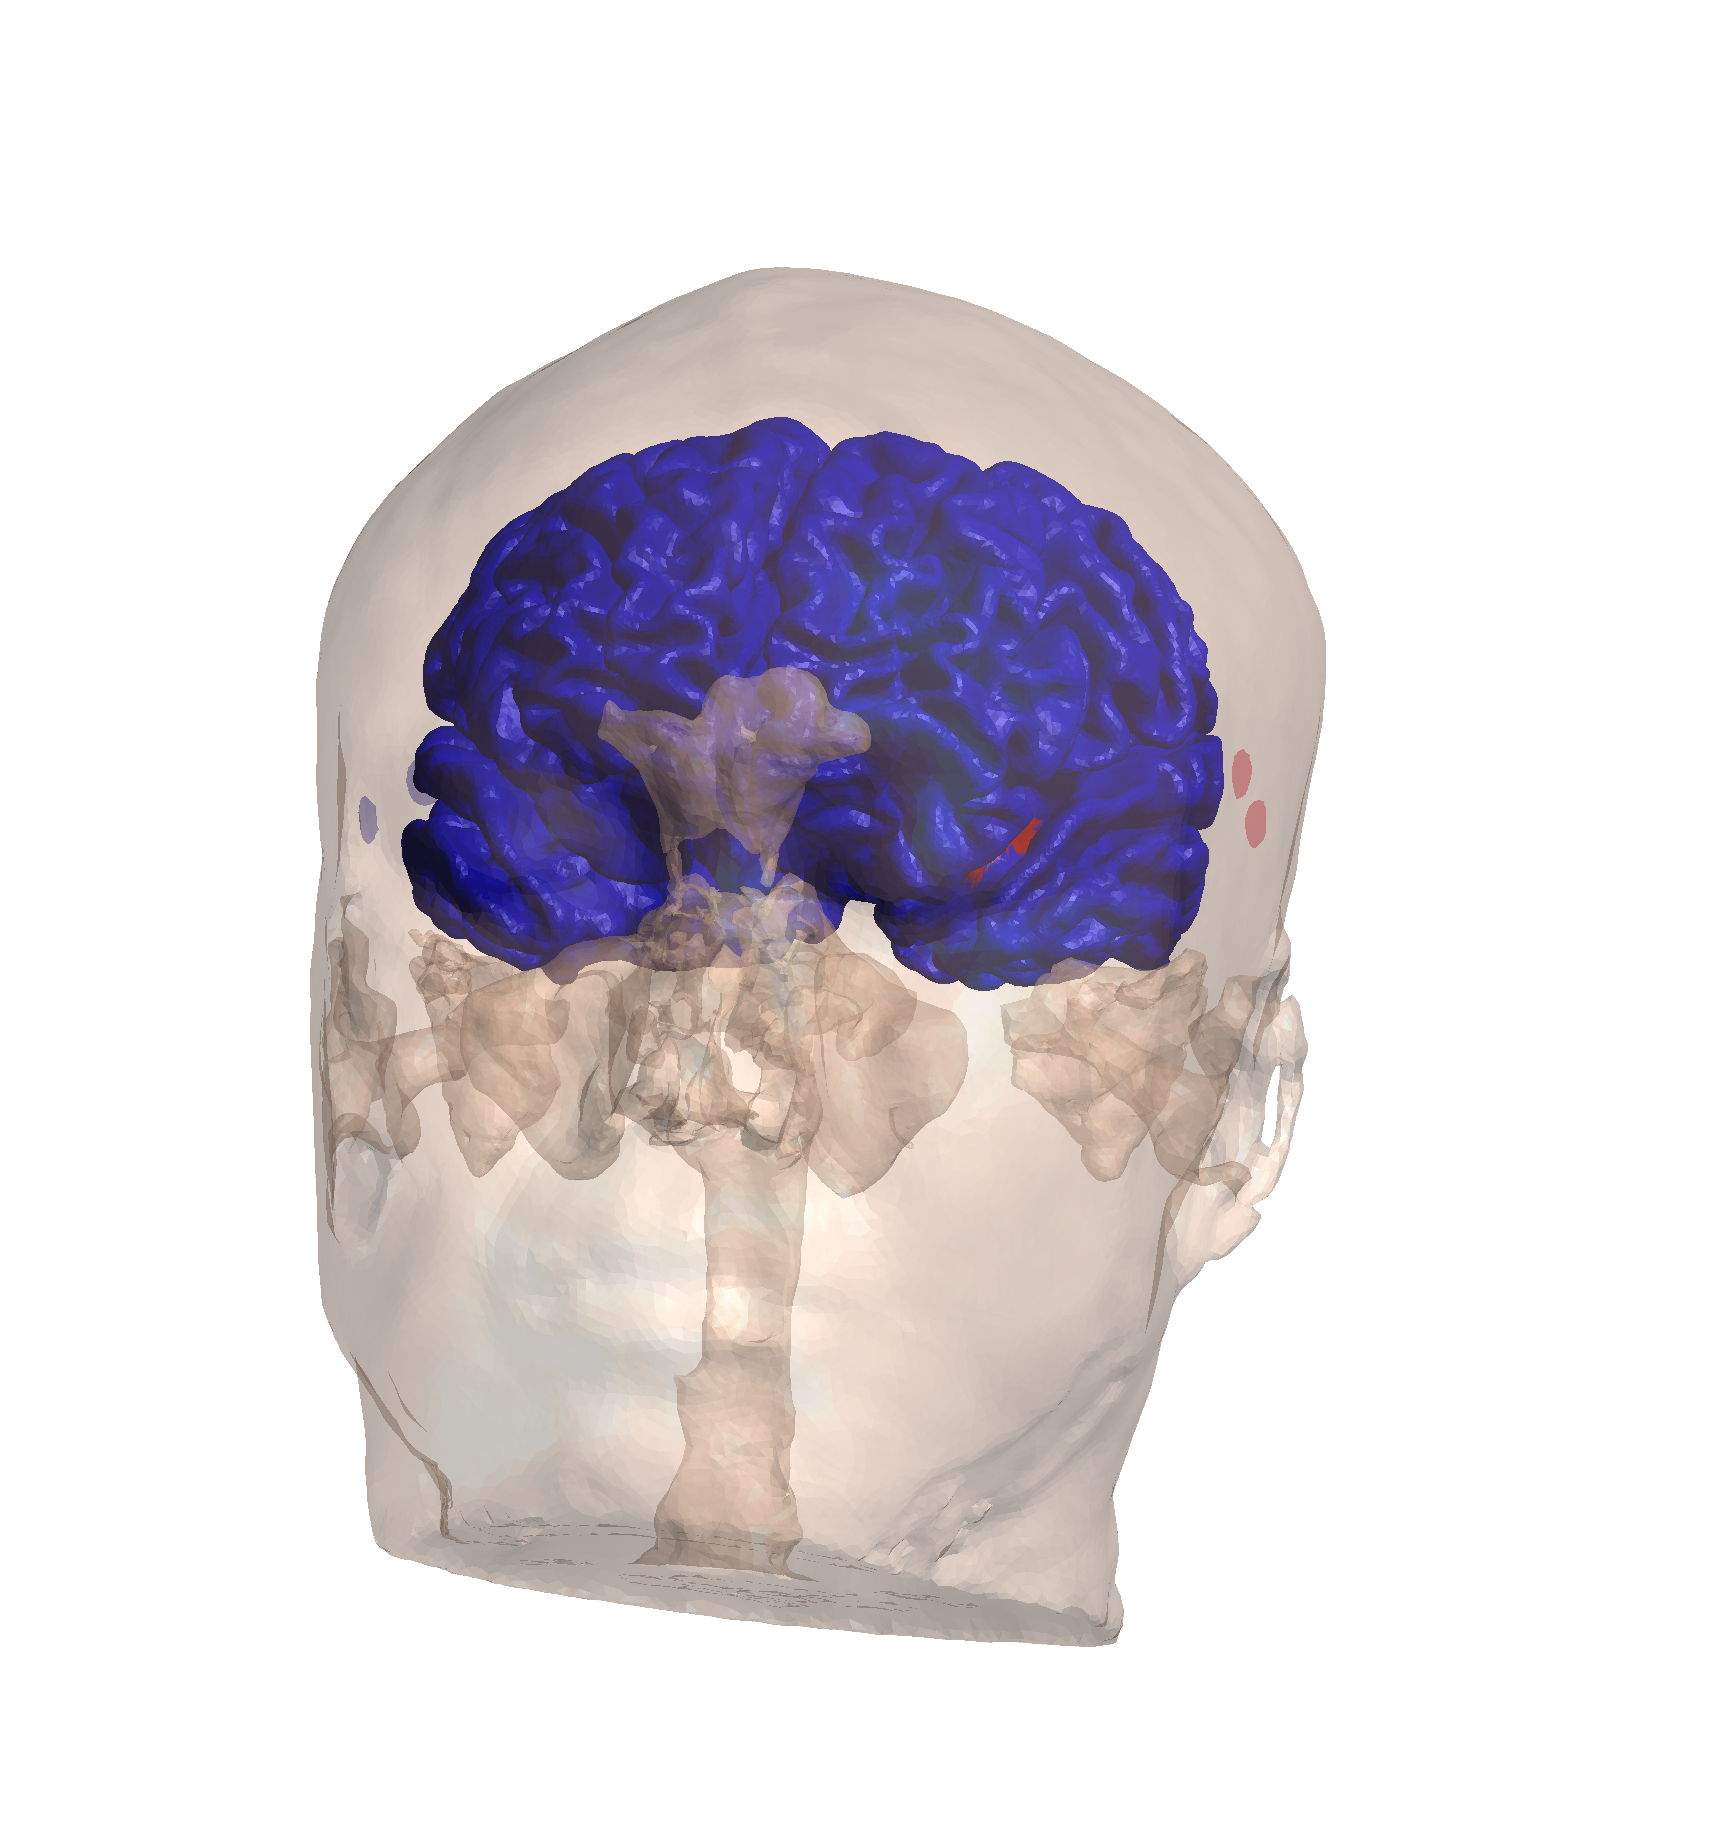

ROI targeting analysis for maximum TI field optimization

ROI targeting analysis for maximum TI field optimization

Optimization Summary:

| Metric | Value |

|---|---|

| Final Goal Value | -2.320 |

| Duration | 25.1 minutes |

| Peak Field (99.9%) | 4.17 V/m |

| Median ROI Field | 2.21 V/m |